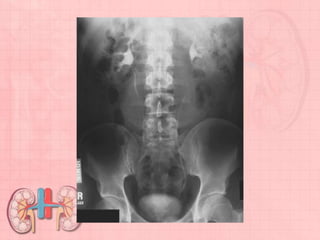

Pathology Demonstrated

Scout demonstrates abnormal calcifications that may be urinary calculi. After

injection, the AP projection may demonstrate signs of obstruction,

hydronephrosis, tumor, or infection.

• Align midsagittal plane to center line of table and to CR.

• Ensure no rotation of trunk or pelvis.

• Include symphysis pubis on bottom of IR without cutting off upper kidneys.

(A second smaller IR for bladder area may be necessary on hypersthenic

patients.)